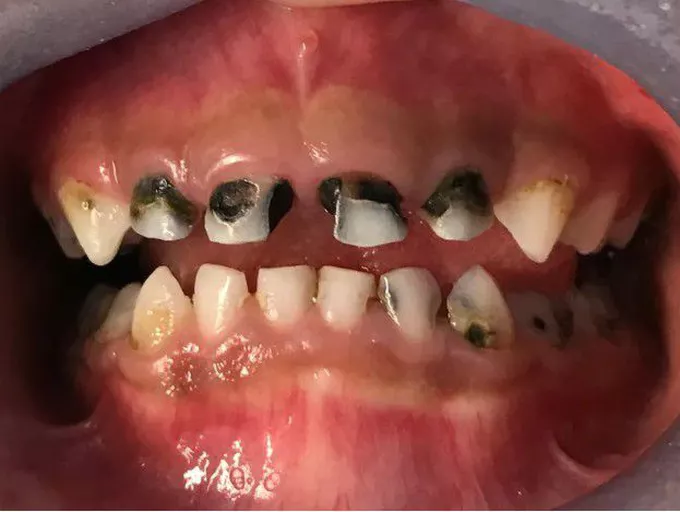

Nursing Baby Syndrome (NBS), atau yang lebih dikenal sebagai Nursing Bottle Caries atau Early Childhood Caries (ECC), adalah bentuk karies gigi pada anak usia dini